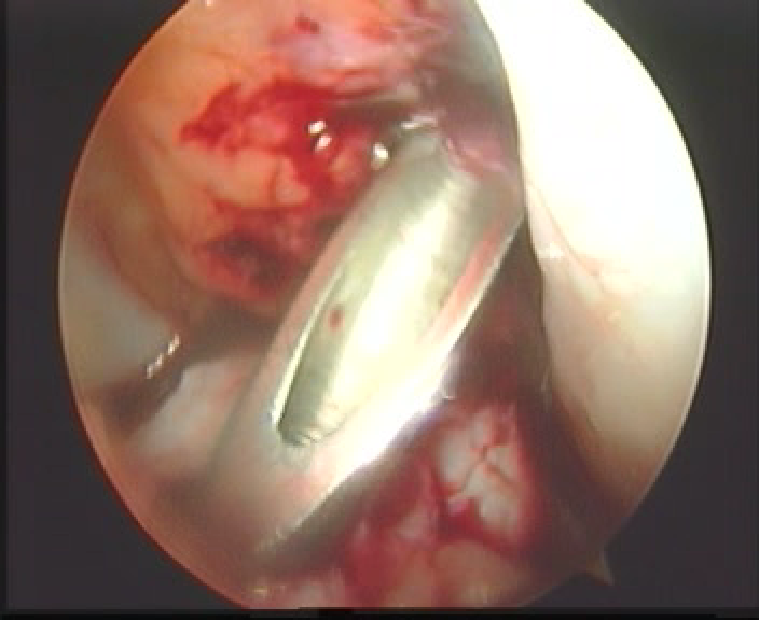

关节镜下观

前交叉韧带损伤后形成的疤痕组织

清理髁间窝

刨削切除ACL残端,以保证视野清晰以及准确定位